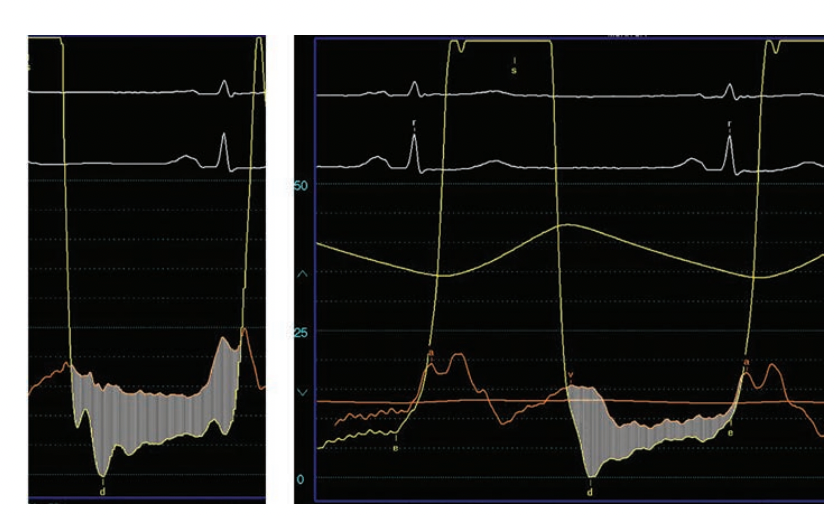

Figure 5 demonstrates the results of PBMV in young patient with low Wilkins scores with reduction of the mitral gradient after a single balloon inflation.

Although occasionally seen, caution in achieving complete resolution of a residual gradient should be used to avoid producing severe mitral insufficiency. In fact, the absence of a gradient after PBMV more commonly correlates with severe mitral insufficiency. The hemodynamics of this example suggest a competent valve; in fact, no mitral regurgitation was detected by echocardiography. It is worth noting that there is often a characteristic minimal peri-commissural leak seen with successful PBMV.

After each inflation, hemodynamics are reviewed for reduction of gradient and induction of any new mitral regurgitation. This is done by a combination of echocardiography (transesophageal or intracardiac echo, and occasionally, by transthoracic echo) and hemodynamics. A decrease in gradient of at least 50% and particularly an increase in mitral insufficiency by one grade should signal the operators to stop. Figure 7 shows this stepwise dilatation technique with an unfortunate result. The initial tracing (Figure 7, left panel) is consistent with severe mitral stenosis in a severely symptomatic woman. After initial inflation the gradient is significantly reduced (Figure 7, middle panel), but the operators continued to attempt to achieve a lower residual gradient. The next inflation with a 1 mm-larger balloon resulted in abolition of the gradient, but produced a giant ‘v’ wave to 70 mmHg (Figure 7, right panel), consistent with severe iatrogenic mitral insufficiency. At surgery to repair the torn valve, a commissure split was the predominant mechanism. The patient did well after emergency mitral valve replacement.